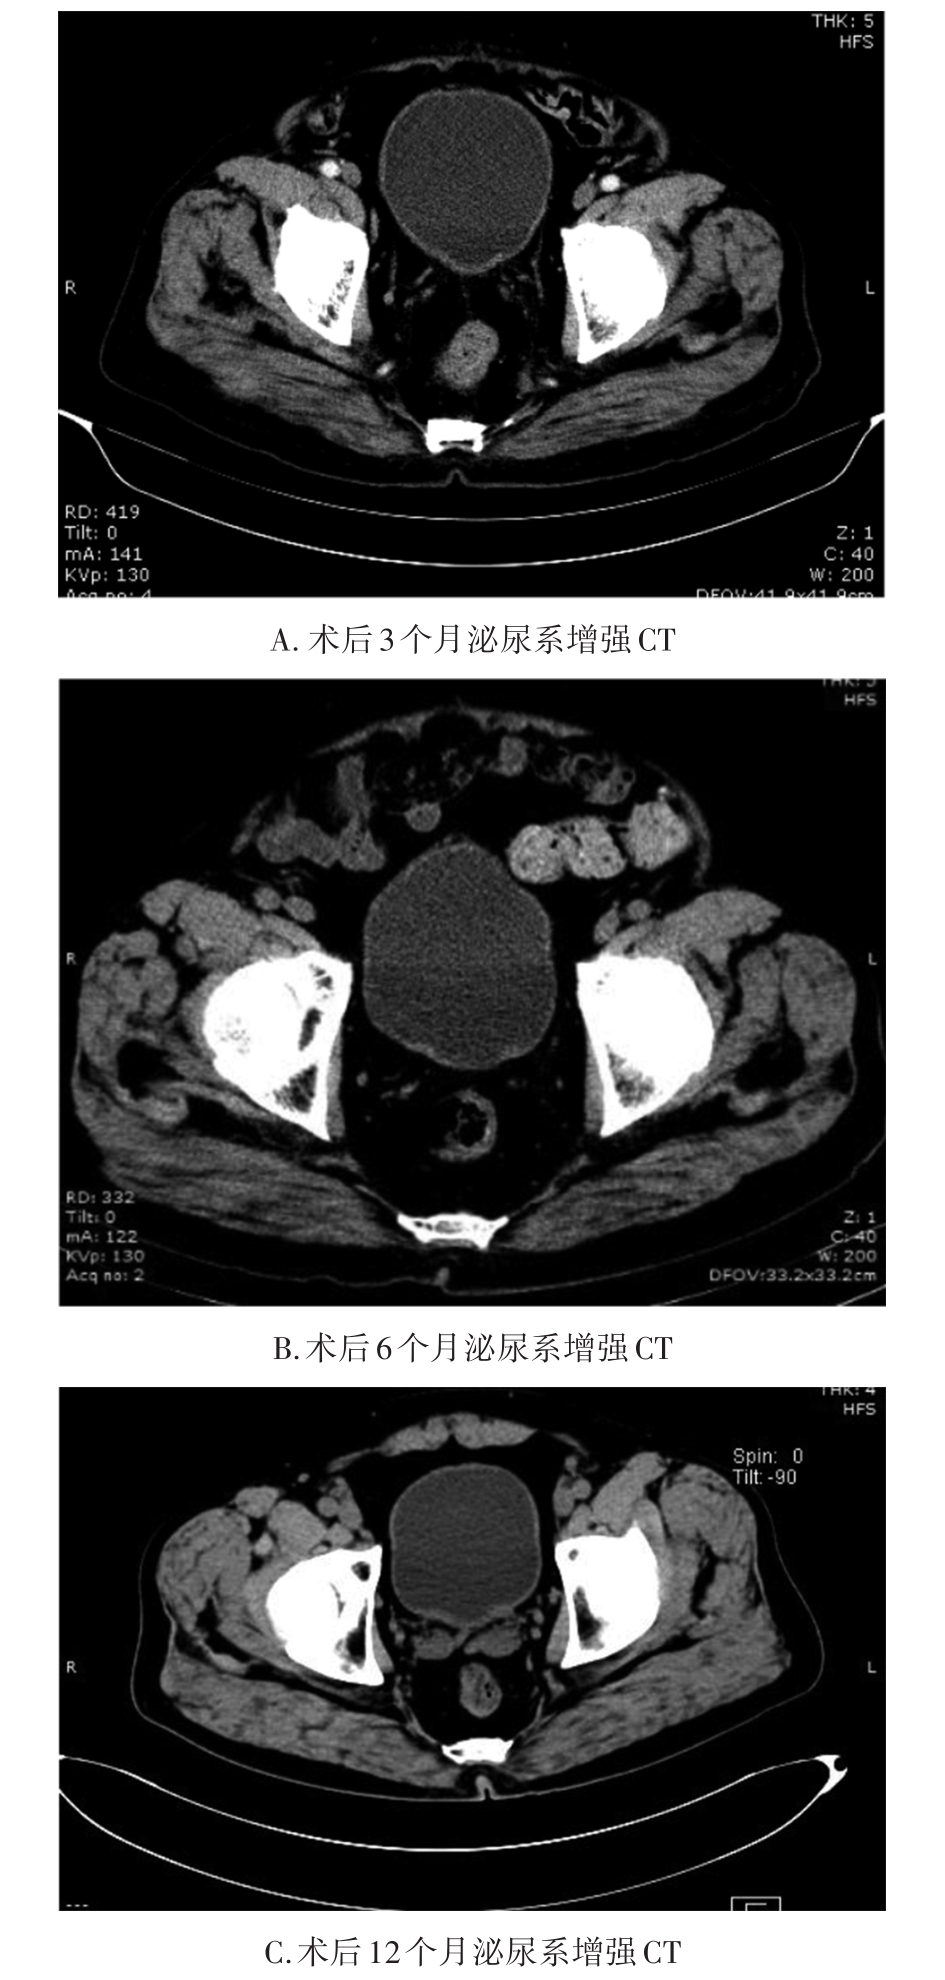

• 转移性上尿路上皮癌在维迪西妥单抗联合替雷利珠单抗新辅助治疗后行根治性肾盂癌切除术1例报道

2023, 48(8):1005-1008. DOI: 10.13406/j.cnki.cyxb.003299

摘要 (52) HTML (36) PDF 2.16 M (1929) 评论 (0) 收藏

摘要: